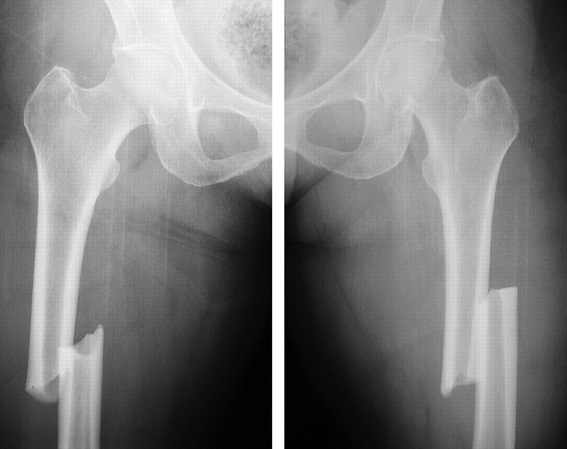

3- تشخیص شکستگی تنه ی استخوان ران: تشخیص قطعی این شکستگی با استفاده از رادیوگرافی ساده داده میشود . باید حتما دقت کرد که مفاصل زانو و لگن در رادیوگرافی دیده شوند. در شکستگی های ران باید با دیدن مفصل ران حتما از عدم وجود در رفتگی مفصل لگن مطمئن شد.

4- درمان شکستگی تنه ی استخوان ران: امروزه تقریبا تمامی شکستگی های ران بالغین با عمل جراحی درمان میشوند. روش کار بدین صورت است که ابتدا شکستگی ران بصورت بسته جااندازی میشود (با استفاده از کشش و مانورهای مخصوصی سعی میشود شکستگی بصورت بسته جااندازی شود. این جااندازی در اطاق عمل انجام شده و پزشک جراح مراحل جااندازی را با استفاده از رادیوگرافی بخصوصی که تصاویر آن مستقیما بر روی مانیتور قابل دیدن است - فلوروسکوپی- کنترل میکند). سپس از راه شکاف های کوچکی که در پوست داده میشود میله داخل استخوانی یا پلاک یا اکسترنال فیکساتور به استخوان متصل شده و آنرا فیکس میکند. به این روش جااندازی بسته و فیکساسیون داخلی یا خارجی میگویند. در صورتیکه جااندازی بسته امکانپذیر نشود پزشک جراح از جااندازی باز استفاده کرده و سپس با روش های پلاک گذاری یا میله گذاری اینترامدولاری شکستگی را فیکس و بی حرکت میکند.